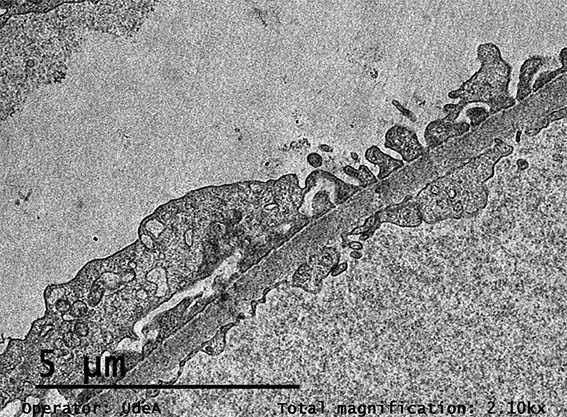

Figura 11. ME, aumento original, X2.100. Procesos podocitarios, membranas basales glomerulares y endotelio normales.

Figura 12. ME, aumento original, X2.100. Paredes capilares glomerulares normales.

Figura 13. ME, aumento original, X2.100.